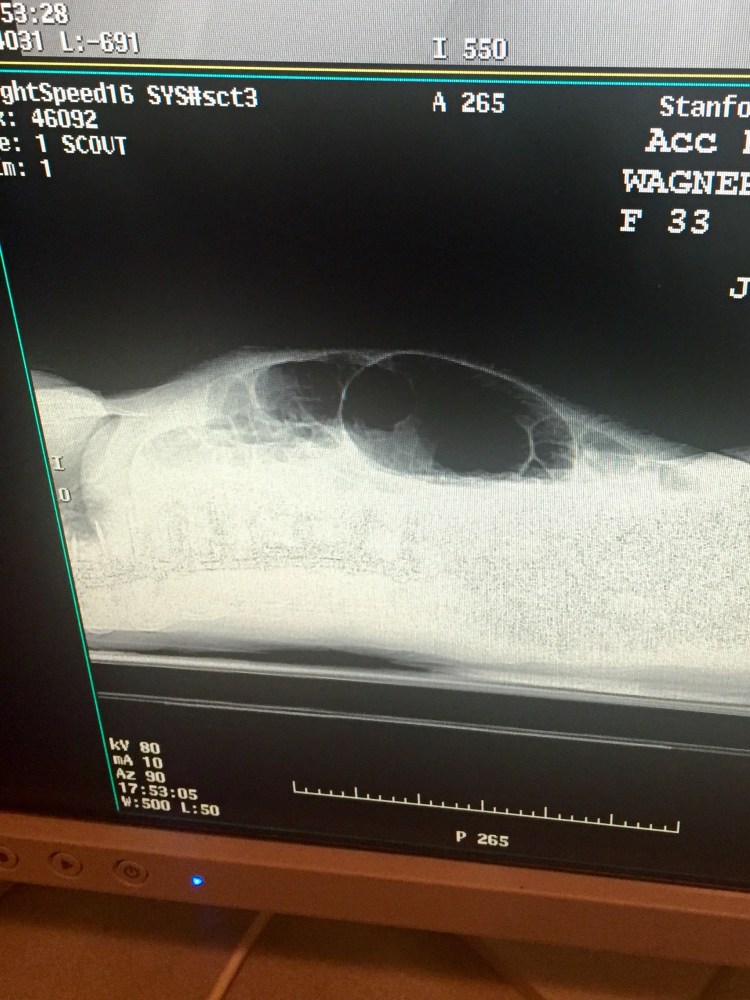

So April has been complaining about abdominal pains for a couple days and she hasn’t been allowed to eat or drink really. Her stomach has been very distended And painful to the touch. Once the MRI was read the Fellow rounded on April and told her the MRI looked great in regards to her spine, but they were concerned about her bowels. He said they were ordering a stat X-ray of her abdomen. The results came back and it looked like she has a large ileus in her bowels, so the doctor wrote orders for her to go to CT stat to get scanned. The CT scan showed she had some very distended bowels, especially her cecum. A colorectal specialist doctor came to see April and told us she has a cecal bascule. A cecal bascule is where the cecum (the beginning of the large intestine) somehow becomes folded over on itself and causes a bowel obstruction. Normally the cecum is about 4cm and April has become distended to 9cm and the only way to fix it is surgery.

Mobile X-ray brought to our room